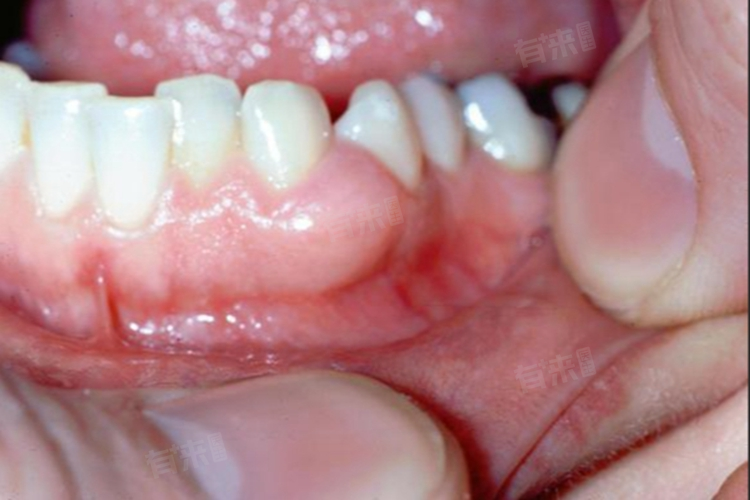

下牙龈外侧长了个硬包是不正常的。牙龈正常情况下应该是粉红色、质地坚韧、表面光滑且连续的,不会出现硬包。

- 牙龈瘤是一种发生在牙龈组织的良性肿瘤,通常由局部刺激因素如牙菌斑、牙结石、不良修复体等长期刺激引起。一般表现为牙龈乳头或边缘龈的局限性增生,质地较硬,颜色可能与正常牙龈相似,也可能呈鲜红色或暗红色,易出血。牙龈瘤的治疗主要是手术切除,同时要去除局部刺激因素,以防止复发。

因此,下牙龈外侧长硬包是不正常的表现,可能预示着多种口腔疾病。如果发现这种情况,应及时到正规的口腔医疗机构就诊,通过详细的检查和诊断,明确病因,并采取相应的治疗措施,以避免病情进一步发展,影响口腔健康和功能。